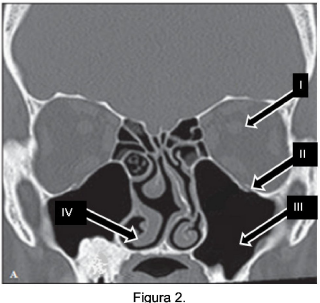

Observe a Figura 2 para responder a questão.

Para uma tomografia computadorizada (TC) dos seios da face, leia as afirmativas abaixo e assinale a alternativa correta.